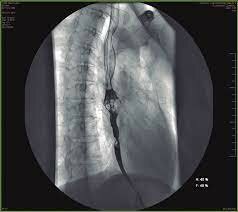

PRIMERA BRAQUITERAPIA ENDOLUMINAL

La primera braquiterapia endoluminal se realizo en Nueva York utilizando fuentes radioactivas de radom que se introdujeron en el tracto respiratorio del paciente para tratar un carcinoma bronquial.